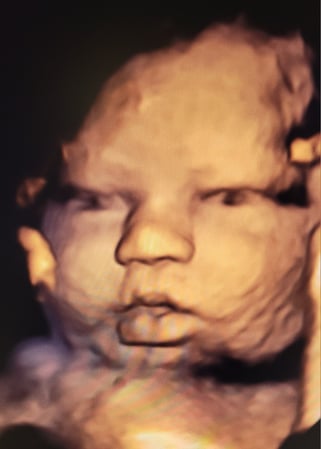

Tasha Crump, is registered by the American Registry of Diagnostic Medical Sonographers (ARDMS) and have over 18 years experience in medical diagnostic sonography specializing in Maternal Fetal Medicine. She is a highly proficient in the art of 3D 4D ultrasound. Tasha has practiced and trained in NYC's top ranked hospitals including Columbia Presbyterian. At Love at First Sight Imaging Studio you'll be in a very comfortable and calming atmosphere for you and your family to bond with your baby. We have state of the art equipment with HD Live to image unbelievably realistic views of your baby. You will fall in Love at First Sight.